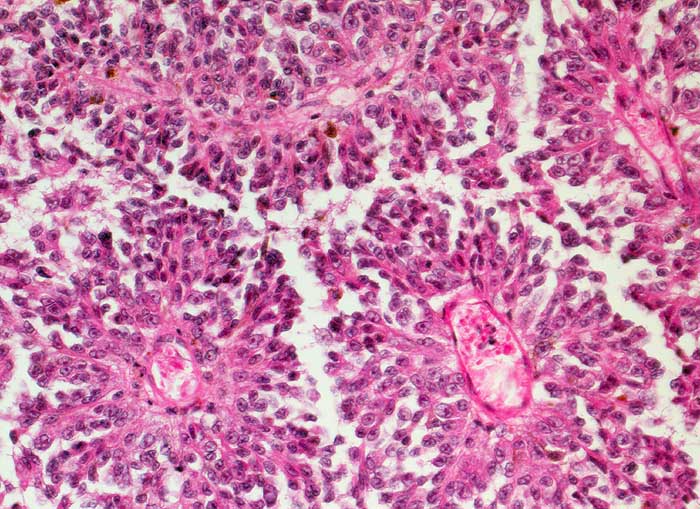

PathoPic – image database / PathoPic ID 6655 - Hirnmetastase malignes Melanom

Hirnmetastase malignes Melanom

Monomorphe Tumorzellen mit kleinen vesikulären Kernen sind pseudorosettenartig um Blutgefässe angeordnet. Vereinzelt sind pigmentierte Zellen erkennbar.

Metastasierendes Melanom.

Histologie

100